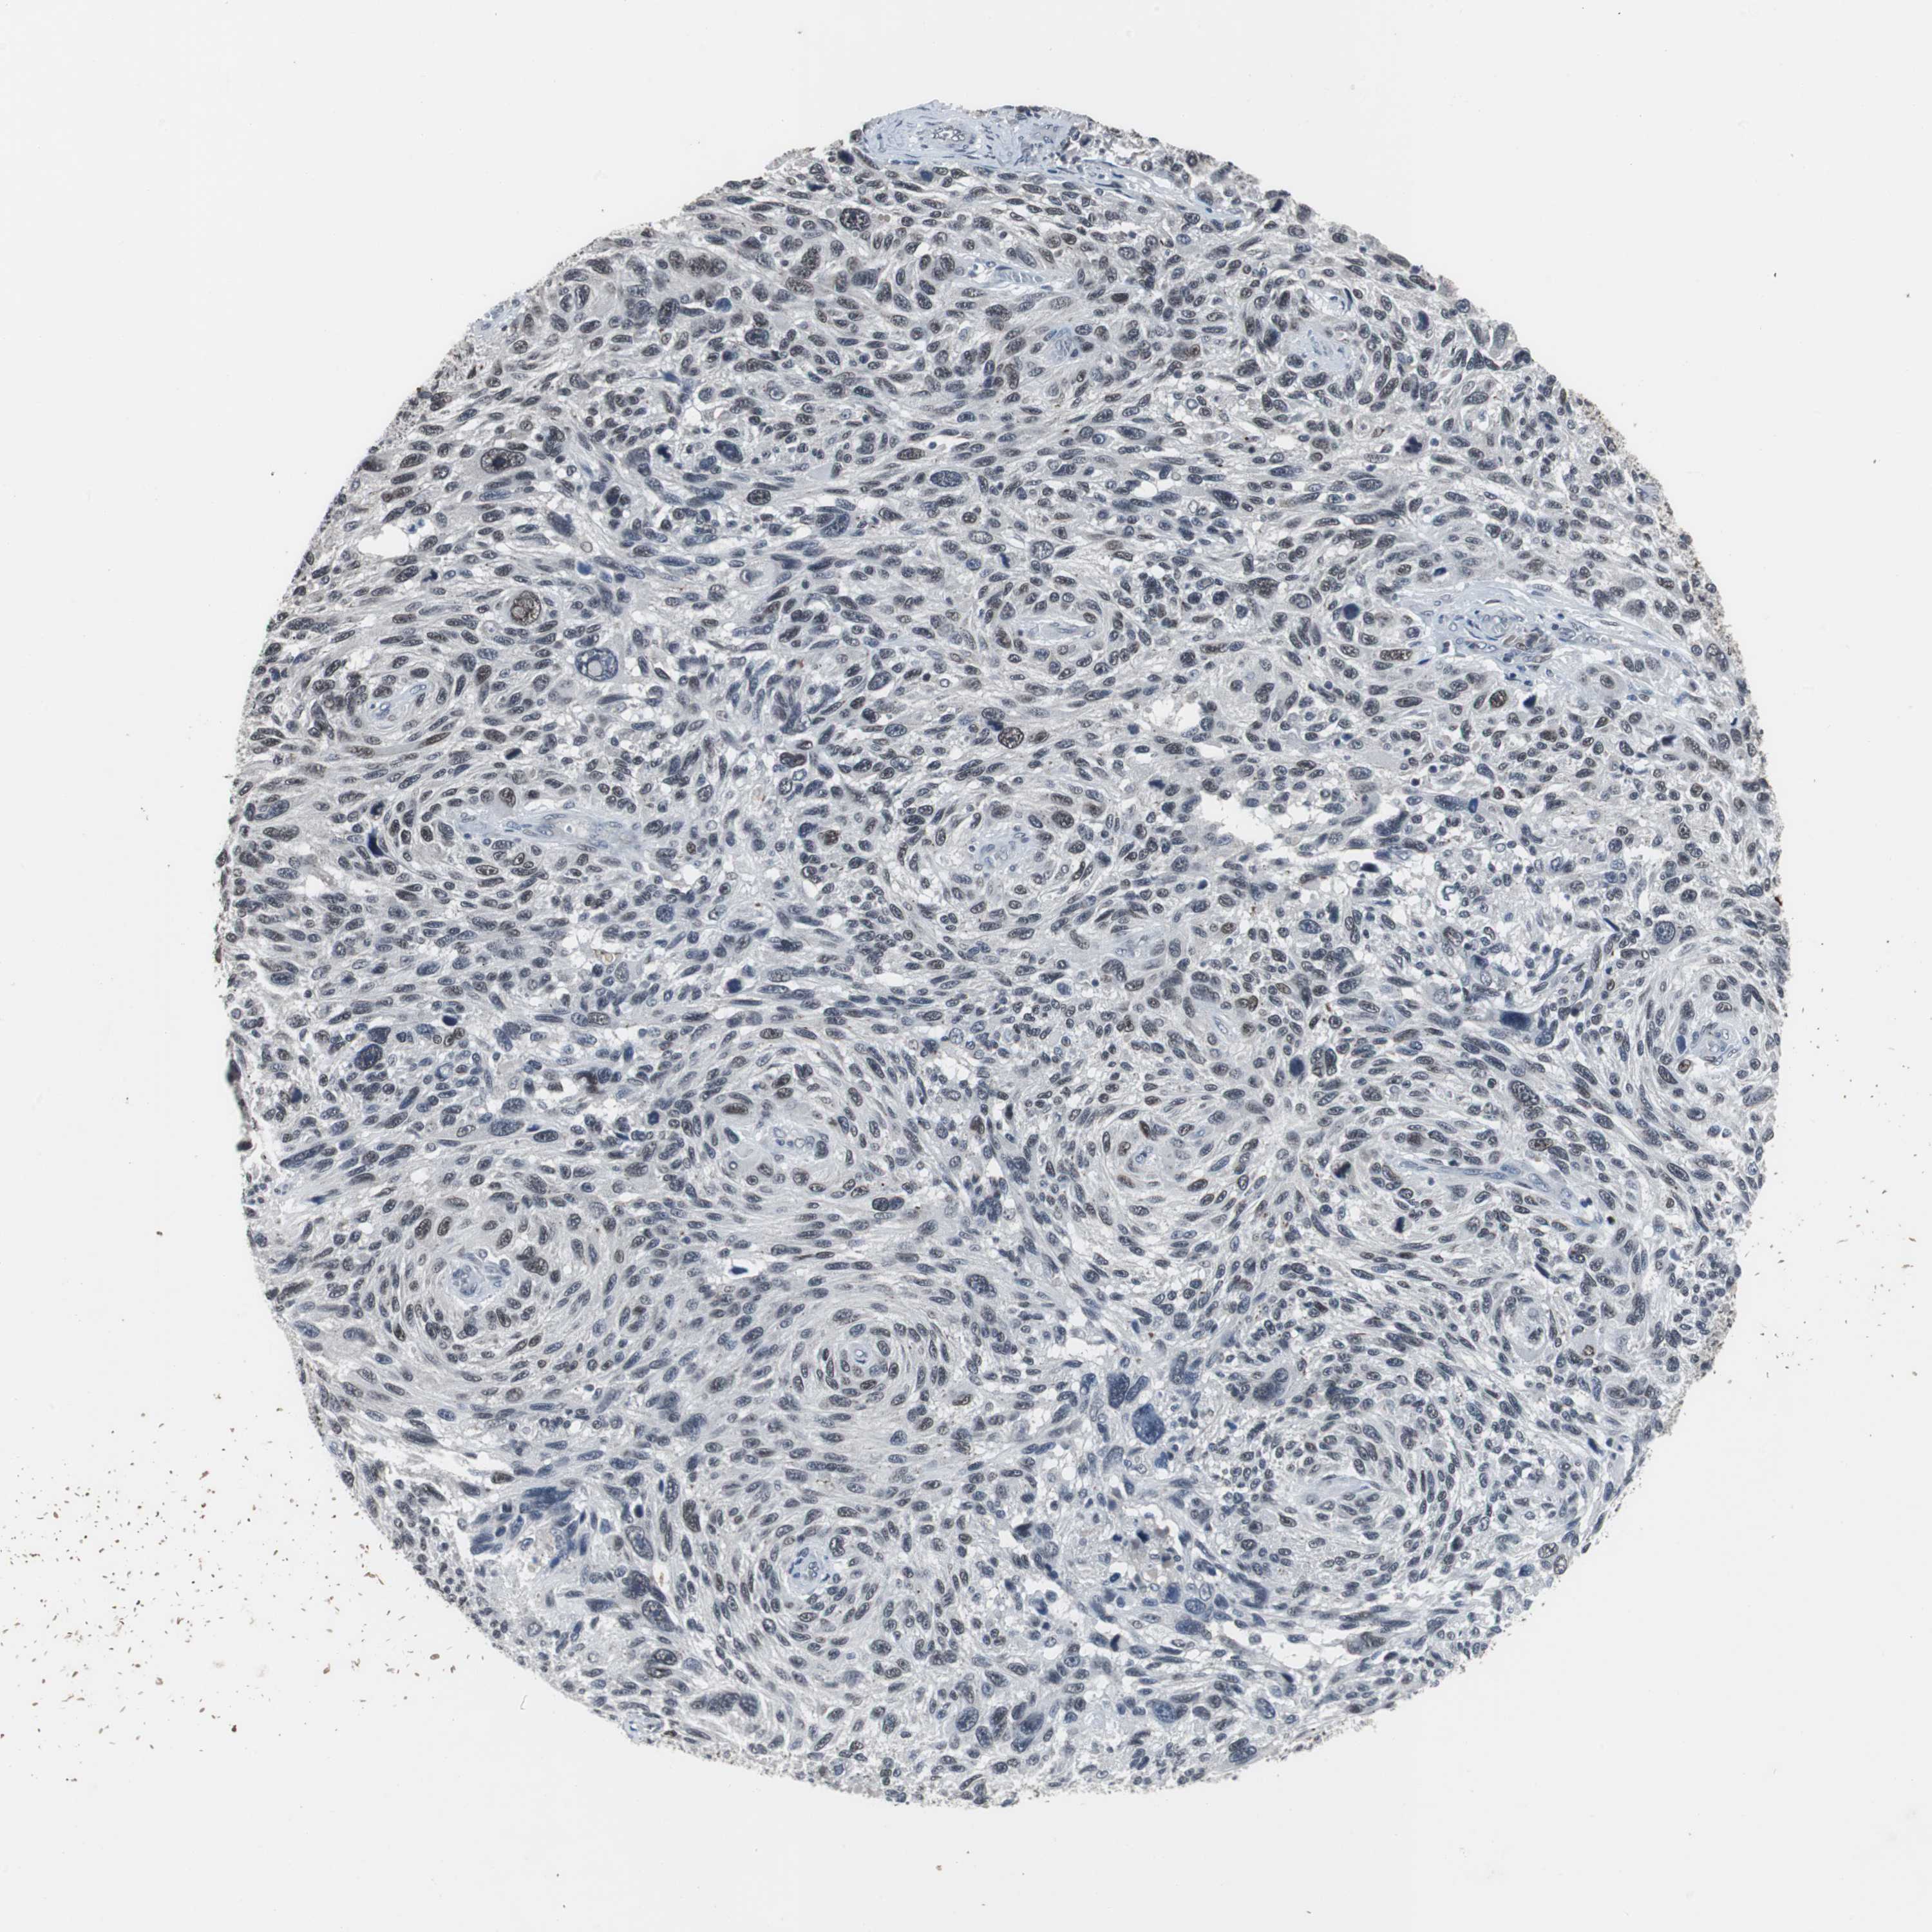

MELANOMA - Protein expressioni

A mouse-over function shows sample information and annotation data. Click on an image to view it in a full screen mode. Samples can be filtered based on level of antibody staining by selecting one or several of the following categories: high, medium, low and not detected. The assay and annotation is described here.

Note that samples used for immunohistochemistry by the Human Protein Atlas do not correspond to samples in the TCGA dataset.

Antibody stainingi

Antibody staining in the annotated cell types in the current human tissue is reported as not detected, low, medium, or high, based on conventional immunohistochemistry profiling in selected tissues. This score is based on the combination of the staining intensity and fraction of stained cells.

Each image is clickable and will lead to virtual microscopy that enables deeper exploration of all samples and also displays staining intensity scores, fraction scores and subcellular localization as well as patient and tissue information for each sample.

Antibody HPA007176

Staining

High

Medium

Low

Not detected

Intensity

Strong

Moderate

Weak

Negative

Quantity

>75%

75%-25%

<25%

None

Location

Nuclear

Cytoplasmic/membranous

Cytoplasmic/membranous,nuclear

Malignant melanoma, NOS

Malignant melanoma, Metastatic site